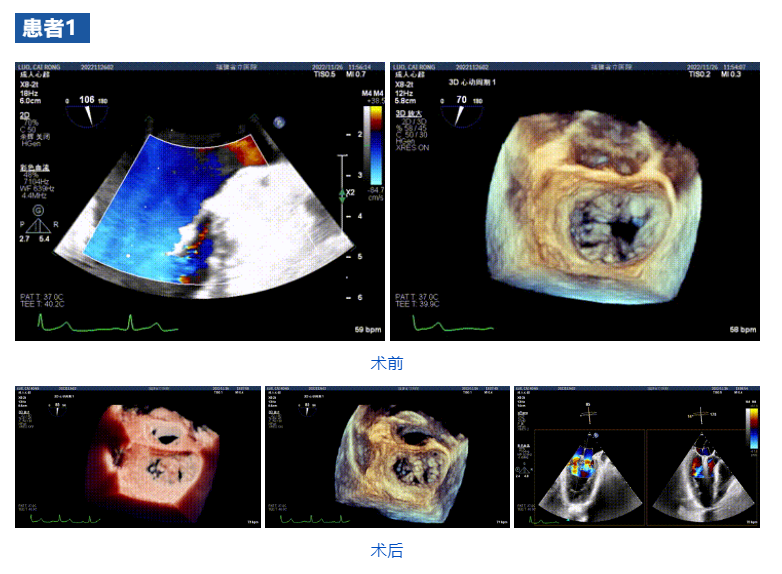

接受治療的三例患者均為器質(zhì)性重度二尖瓣反流(DMR)患者,術(shù)前超聲提示二尖瓣后葉脫垂伴4+反流,左室舒張功能減退。郭延松教授攜同團(tuán)隊(duì)成員陳新敬副教授和洪景宣、方明程、楊清勇主治醫(yī)師、心外科丁杭主任以及超聲科賴(lài)寶春、葉振盛主治醫(yī)師共同進(jìn)行病情討論??紤]到患者高齡、基礎(chǔ)疾病多、STS評(píng)分高,為外科手術(shù)極高?;颊?,不適合進(jìn)行外科開(kāi)胸二尖瓣手術(shù),因此決定為患者實(shí)施經(jīng)導(dǎo)管緣對(duì)緣修復(fù)介入術(shù)(JensClip經(jīng)導(dǎo)管瓣膜夾系統(tǒng))。

在浙江大學(xué)醫(yī)學(xué)院附屬第二醫(yī)院王建安教授團(tuán)隊(duì)的支持下,手術(shù)經(jīng)股靜脈-房間隔入路,采用全身麻醉插管,在TEE和DSA引導(dǎo)下完成房間隔穿刺。置入JensClip瓣膜夾系統(tǒng)后,在左房調(diào)整瓣膜夾的位置和軸向,后進(jìn)入左室,在TEE引導(dǎo)下捕捉二尖瓣前后瓣葉,并關(guān)閉瓣膜夾。經(jīng)TEE反復(fù)確認(rèn)手術(shù)效果后最終鎖定并釋放瓣膜夾。術(shù)后即刻超聲顯示瓣膜夾位置穩(wěn)定,功能良好,二尖瓣反流由術(shù)前4+減少至微量,手術(shù)圓滿成功。